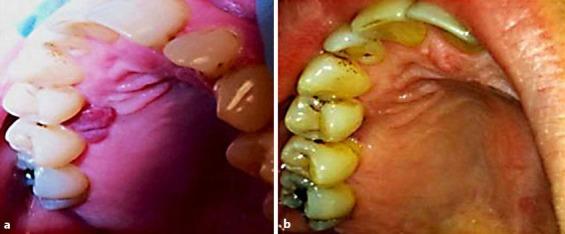

口腔化脓性肉芽肿治疗中的替代治疗方法。

Alternative Therapeutic Approach in the Treatment of Oral Pyogenic Granuloma.

Pyogenic granulomas (PGs) in the oral cavity present as an inflammatory hyperplasia usually caused by trauma, hormonal imbalance, chronic irritation, or as the response to a wide variety of drugs. PGs with atypical presentation and behavior may clinically mimic malignant tumors. Thus, histological examination is required to rule out cancer development. Lesions in the oral cavity have been described to be either an isolated entity or present in multiple forms and with multiple recurrences. Conservative surgical excision is the standard choice of treatment in almost every scenario. However, the severity of the lesions and the affected sites often challenge surgical treatment. In this report, we describe the clinical scenario of a recurrent PG, where surgical excision of the lesion was questioned. As an alternative, we describe a noninvasive approach with lesional steroid injections.

口腔化脓性肉芽肿(PGs)表现为一种炎症性增生,通常由创伤、激素失衡、慢性刺激引起,或作为对多种药物的反应。具有非典型表现和行为的PGs在临床上可能类似于恶性肿瘤。因此,需要进行组织学检查以排除癌症发展。口腔病变已被描述为孤立的实体,或呈多种形式并多次复发。在几乎每种情况下,保守性手术切除都是标准的治疗选择。然而,病变的严重程度和受累部位常常对手术治疗构成挑战。在本报告中,我们描述了一例复发性PG的临床情况,其中对病变的手术切除提出了质疑。作为一种替代方法,我们描述了一种病灶内注射类固醇的非侵入性方法。